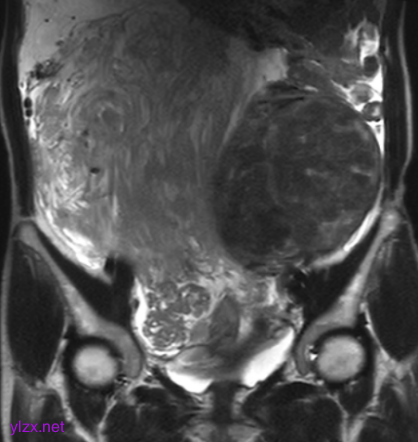

MRI检查:

子宫右侧巨大实性占位,大小约260×110×91mm,与子宫分界不清,T1WI呈稍低信号,T2WI呈不均匀稍高信号,呈束状、旋涡状改变(图1),病变内部分可见囊变,肿瘤内部及表面多发流空血管影(图2);DWI上病变呈略高信号,ADC图呈略低信号,ADC值为1.633×10-3 mm2 /s;增强扫描呈明显强化(图3),内部见条片状低信号。影像学考虑子宫右侧恶性肿瘤。

图1

图2

图3

子宫PEComa影像学表现各异,其MRI表现具有一定的特征,肿瘤T2WI信号稍高,呈束状排列,富血供,可伴有变性、坏死,肿瘤内部及表面可见多发流空血管影。